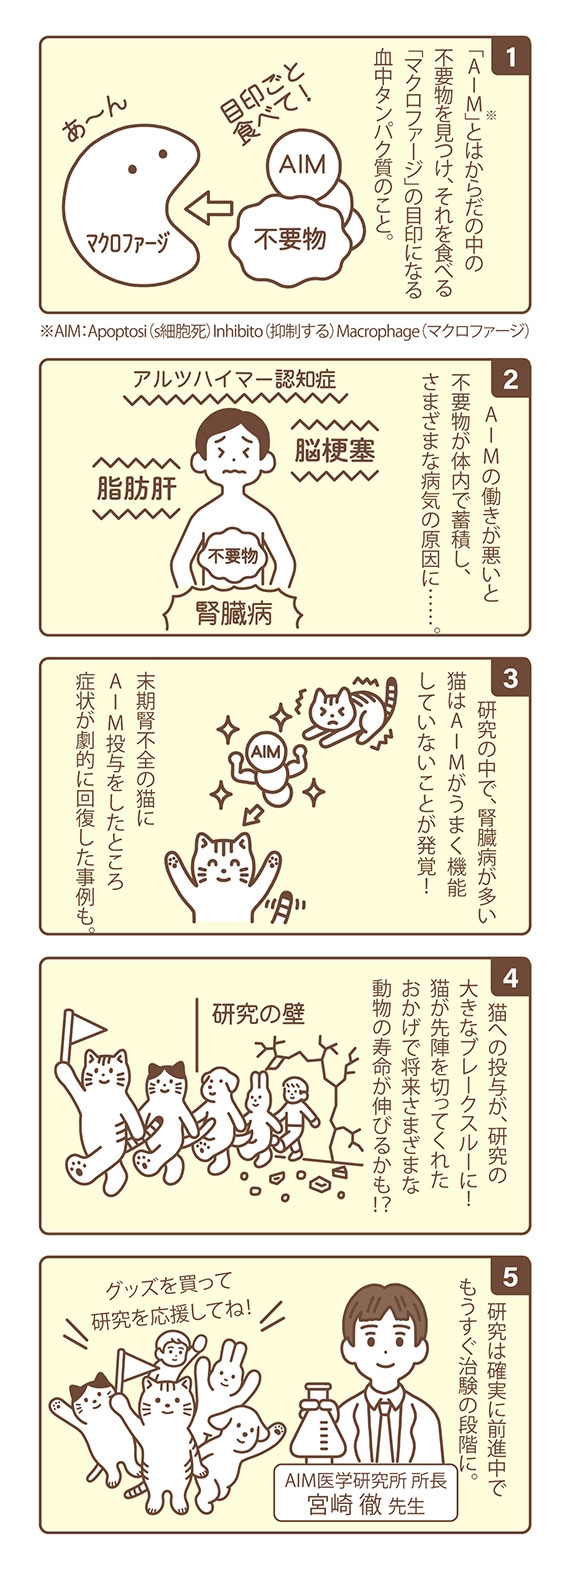

腎臓病診療の最先端No.30, サポーターになって応援しよう!猫の,

サポーターになって応援しよう!猫の, Impella RP Flex with SmartAssistが右心不全の治療としてFDA,

Impella RP Flex with SmartAssistが右心不全の治療としてFDA, 猫の腎臓病治療薬開発につながる「AIM医学研究」を支援する,

猫の腎臓病治療薬開発につながる「AIM医学研究」を支援する, Impella RP Flex with SmartAssistが右心不全の治療としてFDA,